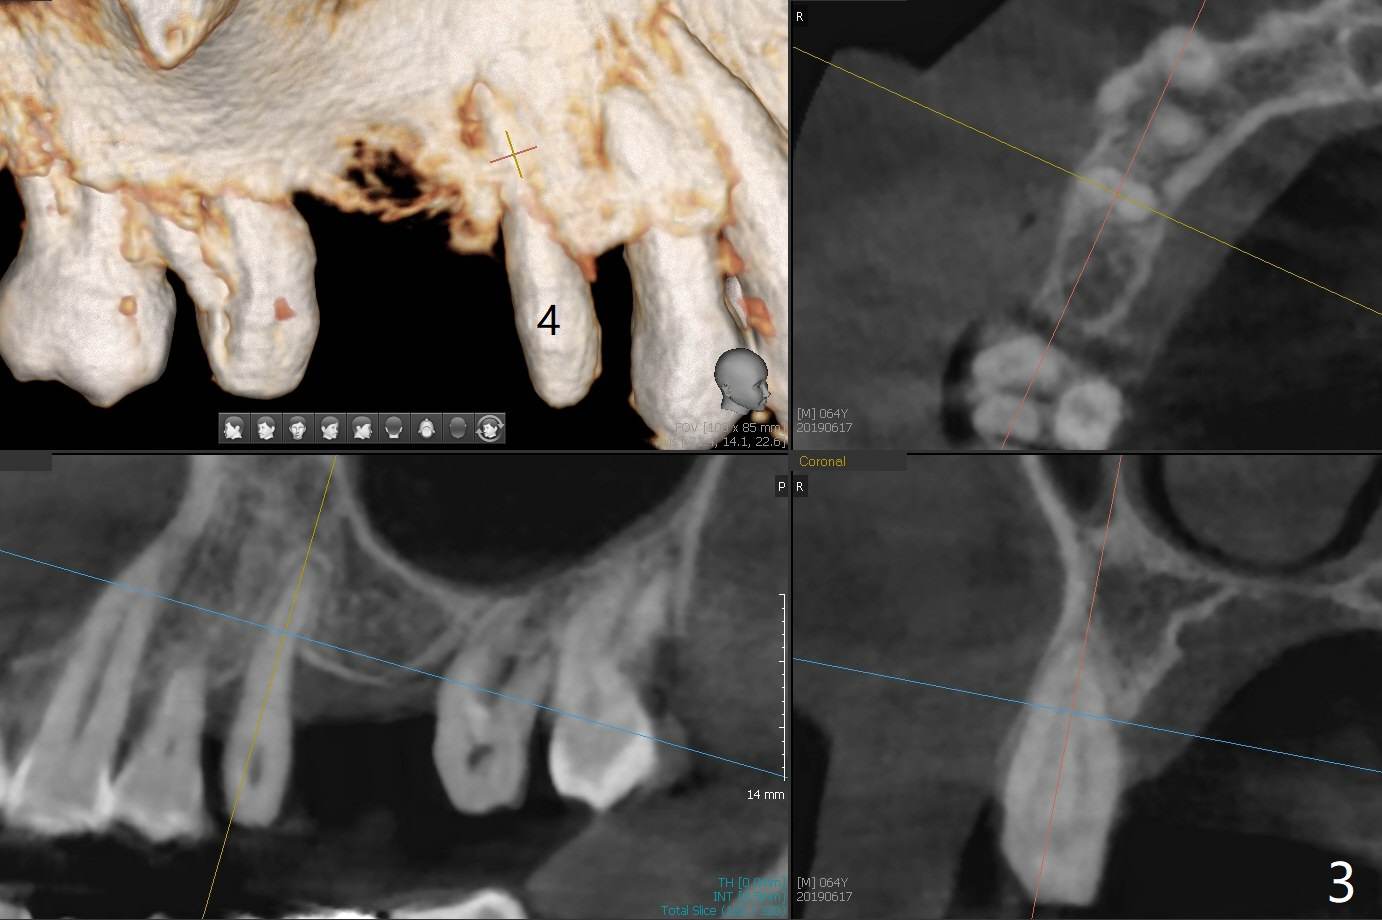

A 64-year-old man has a loose FPD at #2-4. After discussion, he agrees to have it removed for implant at #3 (Fig.1). In fact the bone loss at #2 is severe (Fig.2, as compared to #4 (Fig.3)). When the implant osteointegrates (Fig.4), make single unit crowns and let the patient decide whether the tooth #2 is salvageable or not.